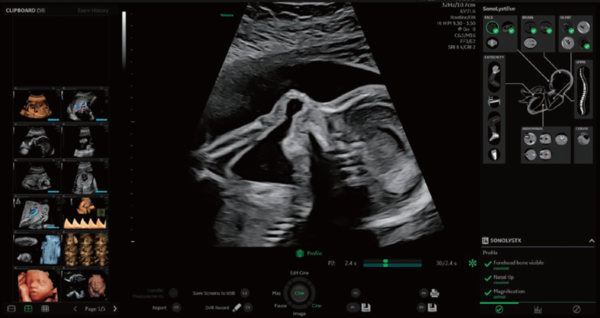

SonoLystは,ワークフロー改善のためにAI手法を用いて開発されたソフトウェア。ISUOG(国際産婦人科超音波学会)ガイドラインに準拠し,解剖学的な特徴からスキャン中の描出断面が基準断面にどれほど近づいているかを知らせて医師のスキャンをサポートする。フリーズ後は,ガイドラインの基準断面に即したどの部位であるかを自動認識し,ユーザーに提案し,ユーザーがそれを受け入れると,チェック済項目として保存される。これにより,胎児スクリーニング検査の効率化と検査クオリティの担保,ユーザーの自己学習の推進に貢献する。

SonoLystを用いた検査画面